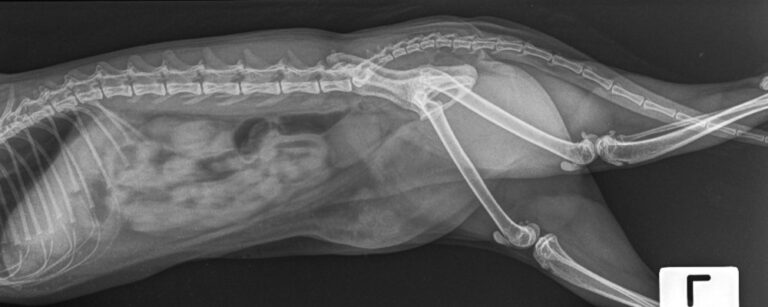

Our digital X-ray technology provides crystal-clear images that reveal internal structures, fractures, foreign objects, and organ abnormalities with remarkable detail. Laboratory analysis covers blood chemistry, complete blood counts, urinalysis, and specialized tests that detect diseases before symptoms become severe.